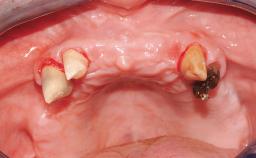

Conventional Loading of Six Implants in the Mandible and Final Restoration with a Full-Arch Metal-Ceramic FDP

A 68-year-old, completely edentulous male patient presented for evaluation and treatment options. He reported excellent general health and was taking no regular medication. He had been edentulous for approximately 12 years, having lost his teeth to periodontal disease and dental caries. The patient’s chief complaint was incompetent function. His secondary concerns included his appearance and the desire for a predictable outcome. He attributed his reduced functional capacity to his lower complete denture, which he described as poor. He was particularly concerned with the denture’s instability and poor fit. In general terms, he was satisfied with the maxillary complete prosthesis. The maxillary prosthesis was characterized by adequate retention, stability, and support, although the fit was considered less than ideal.

Case Type Edentulous Mandible

Jaw Mandible

Area Full-Arch